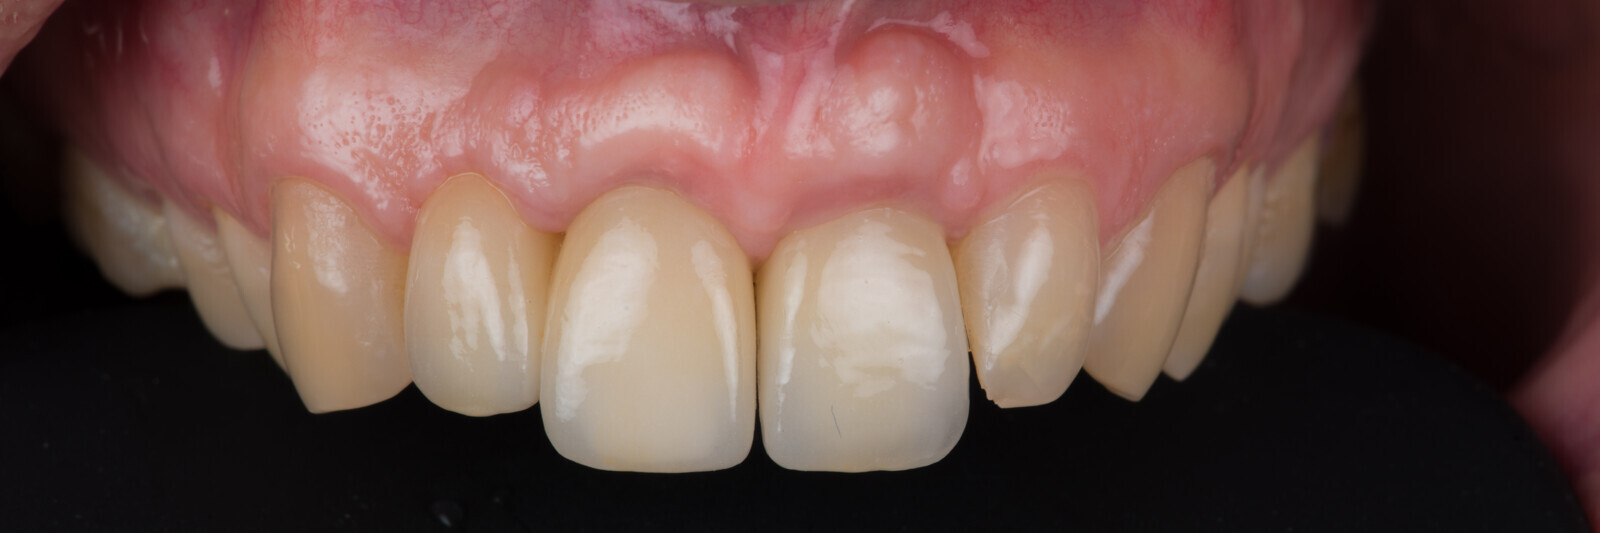

Immediate placement and restoration of a Straumann BLX implant replacing maxillary incisors